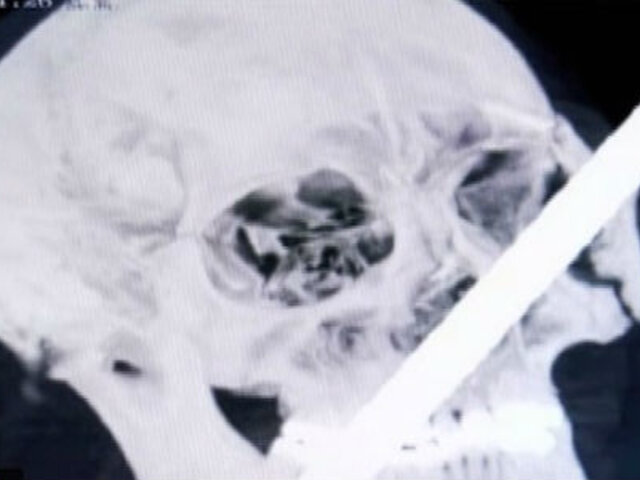

El obrero de construcción Anderson Chavarría Sinche se recupera luego de ser operado exitosamente en Clínica Internacional. Fierro le atravesó la cabeza cuando ayudaba en una obra en Tarma.

De emergencia fue trasladado a Lima el obrero que terminó con un fierro incrustado en el rostro. Hoy fue operado con éxito en una clínica de la capital.